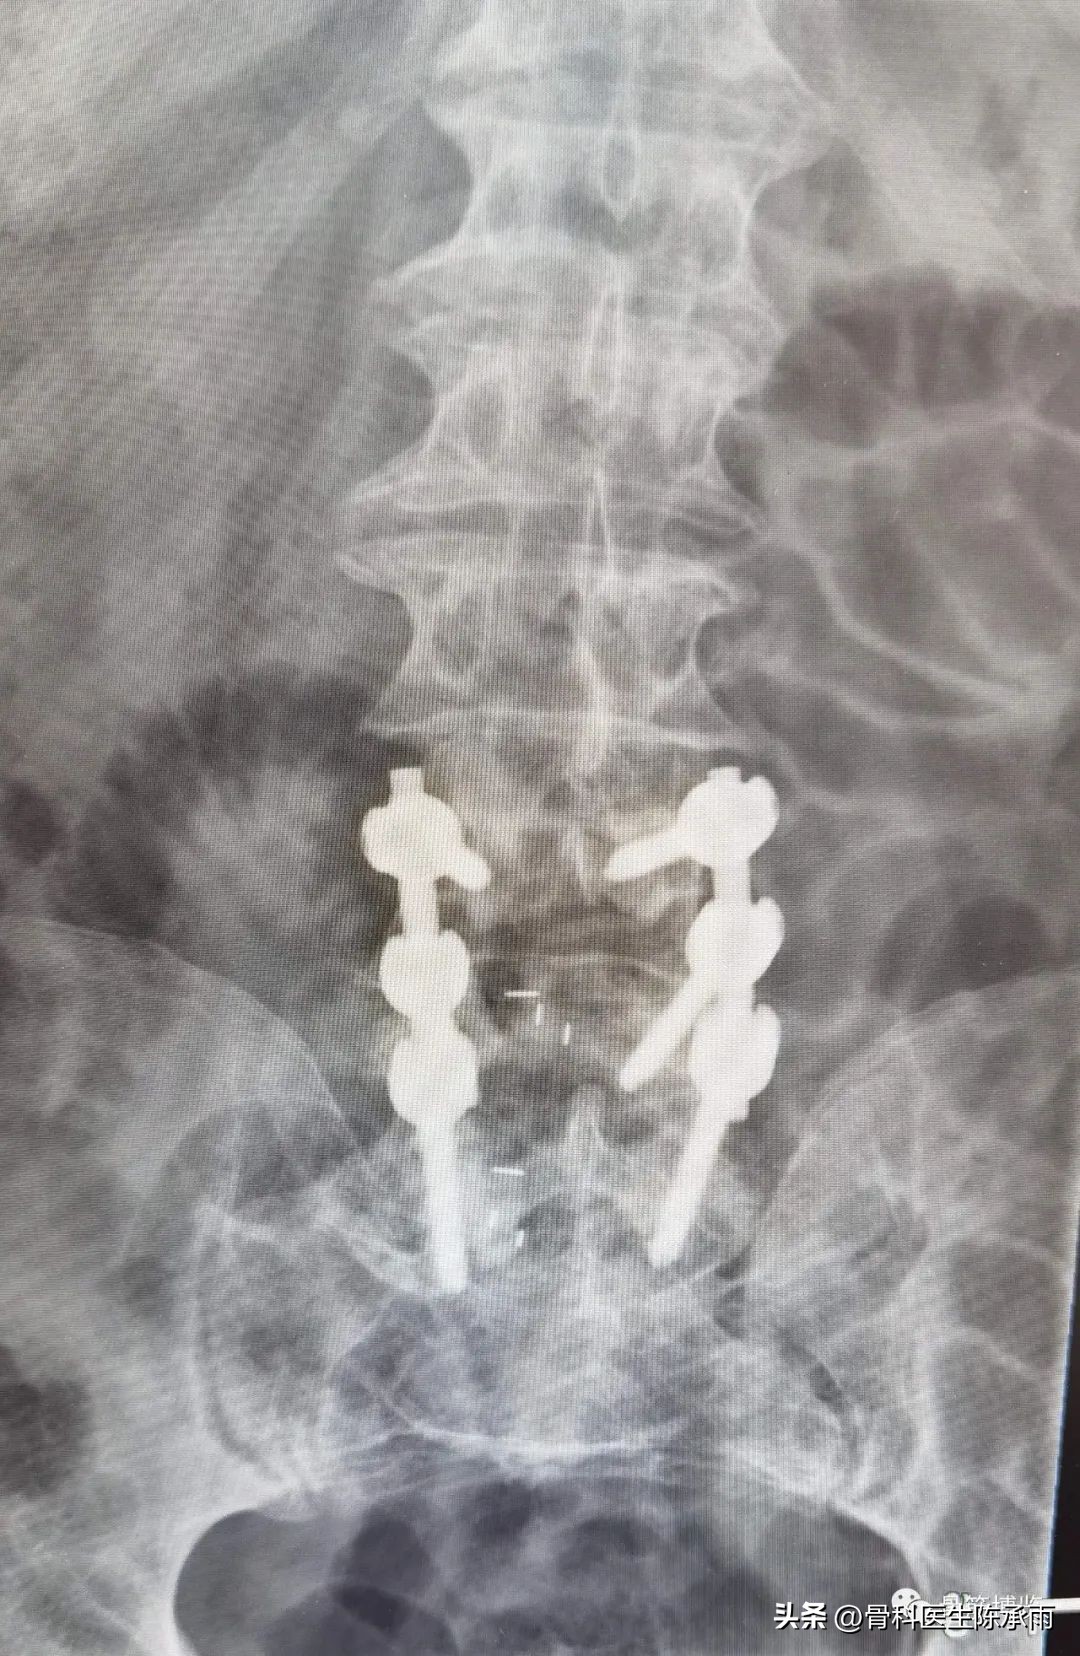

术中固定情况:后路全椎板减压,钉棒固定,两个间隙的椎间融合

术后影像